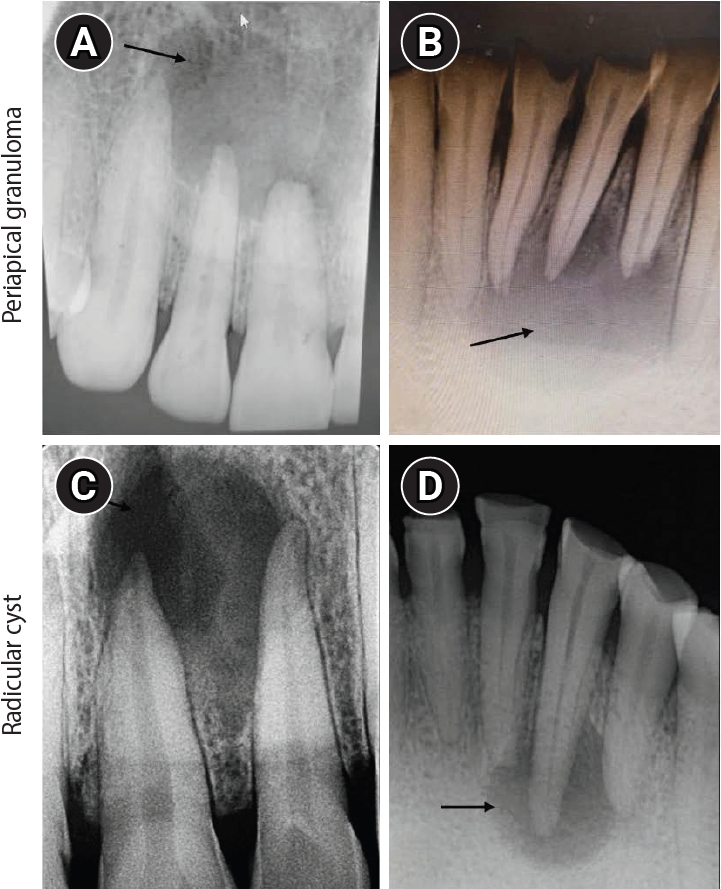

All samples underwent macroscopic examination and were appropriately grossed to allow a comprehensive histological analysis of periapical lesions. Tissue sections, 4 μm thick, were prepared from formalin-fixed, paraffin-embedded blocks of HP, PG, and RC. These sections were mounted on glass slides, stained with hematoxylin and eosin, and examined under light microscopy (A, B, and C panels of Figures 35). Histopathological evaluation focused on characteristic features such as the epithelial lining, inflammatory cell infiltrate, and connective tissue organization, which formed the basis for the definitive diagnosis of RC, PG, or HP. The histopathologic diagnosis was performed by experienced oral pathologists.

1. Hypoxia-inducible factor-1α expression

Stronger cytoplasmic and intense nuclear staining of HIF-1α was observed in all samples of PG and RC compared to HP (D, E, and F panels of Figures 35). In PG and RC, staining was prominent in inflammatory cells, including macrophages, lymphocytes, and polymorphonuclear neutrophils, as well as in endothelial cells and fibroblasts. Additionally, all layers of the epithelial lining of RC and inflammatory cells within the cystic capsule showed positive staining. However, in HP, HIF-1α staining was limited to fibroblasts and endothelial cells (Figures 35). The mean HIF-1α expression was highest in PG, followed by RC and HP, and their comparison was significant (p < 0.001) (Table 2). Upon applying the Mann-Whitney test for intergroup comparison, expression of HIF-1α was significantly higher in PG and RC than in HP (p < 0.001 for both), while that between PG and RC was not significant (p = 0.865) (Table 3).

2. Vascular endothelial growth factor expression

VEGF was evaluated in blood vessels, inflammatory infiltrate (mainly lymphocytes, plasma cells, and neutrophils), and stromal cells (fibroblasts). Overall, VEGF exhibited pronounced cytoplasmic positivity across all study groups. Immunohistochemical assessment was conducted in the connective tissue of PG, RC, and HP, as well as in the epithelial lining of RC (G, H, and I panels of Figures 35). VEGF expression was highest in RC than in PG and HP, and this difference was significant (p < 0.001) (Table 2). Upon intergroup comparison, the expression of VEGF was significantly higher in PG and RC than in HP (p < 0.001 for both); however, the difference between PG and RC was not significant (p = 0.454) (Table 3). The analysis of VEGF immunoreactivity in the epithelium of RCs revealed weak expression in one case (5.9%), moderate expression in six (35.3%), and strong expression in 10 cases (58.8%).

3. CD68 expression

Both lysosomal granules and the surface of macrophages expressed the CD68 antibody. Macrophage immunostaining was more prominent in the subepithelial regions of RC and the middle areas of PG (J, K, and L panels of Figures 35). The mean CD68 expression was significantly higher for RC than PG and HP (p < 0.001) (Table 2). Upon intergroup comparison, the expression of CD68 was significantly higher in RC and PG than in HP, and significantly higher in RC than in PG (p < 0.001, p < 0.001, and p = 0.018, respectively) (Table 3).

The proliferation of cells and formation of cellular aggregates in periapical lesions can restrict oxygen diffusion to the lesion center, leading to hypoxia [15]. In the present study, HIF-1α expression levels were highest in PG, followed by RC, and least in HP, which was significant (p < 0.001) (Figures 35). The comparison of HIF-1α expression between HP and PG and HP and RC was also significant (p < 0.001 for both); however, the intergroup comparison between PG and RC was not significant (Tables 2 and 3).

Huang et al. [3] also reported higher HIF-1α expressions in PG and RC compared with HP, with no significant difference between PG and RC. Their values were higher than those in the present study, likely due to differences in lesion size, inflammation, and genetic factors. It could be hypothesized that the elevated HIF-1α in PGs may result from increased inflammatory activity, in which macrophages and lymphocytes create a hypoxic microenvironment via cytokine release, particularly IL-1β (Figure 3). In contrast, RCs experience hypoxia due to ischemia from cystic cavity formation but have lower inflammation-driven hypoxia (Figure 4) [3].

Conversely, Alsaegh et al. [15] and da Costa et al. [14] found significantly higher HIF-1α in RC, attributing it to epithelial proliferation, ischemic microenvironment, and increased metabolic demand. The cystic structure restricts oxygen diffusion, stabilizing HIF-1α. Based on the present study findings, it could be hypothesized that higher HIF-1α expression in PG than RC may be due to the acute and dynamic inflammatory environment in PG, which increases metabolic demand and oxygen consumption, intensifying hypoxia. The intense immune cell infiltration and active tissue remodeling in PG further amplify HIF-1α expression. Also, the fluctuating oxygen levels in PG may drive transient HIF-1α activation, whereas the more stable, chronic hypoxia in RC results in relatively lower expression. The lack of an epithelial lining in PG could also allow broader HIF-1α expression across stromal and inflammatory cells. The expression levels in PG and RC were comparable, with no significant difference, although the PG group showed slightly higher values. Thus, there was a hypoxic environment in both RC and PG, albeit this was slightly higher in PG due to a greater inflammatory response.

HIF-1α is closely linked to the VEGF pathway, with its connection being evident across various physiological and pathological conditions [15]. Activation of HIF-1α directly upregulates VEGF expression, playing a pivotal role in stimulating new blood vessel formation and supporting tissue repair through angiogenesis [15]. VEGF expression levels were highest in RC, followed by PG, and lowest in HP, with a significant difference (p < 0.001) (Figures 35). The comparison of VEGF expression of HP with PG and RC was significant (p < 0.001 for both) and not significant for PG and RC (p = 0.454) (Tables 2 and 3).

Figure 4.

Hematoxylin and eosin (H&E) and immunoexpression of hypoxia-inducible factor 1 alpha (HIF-1α), vascular endothelial growth factor (VEGF), and CD68 in radicular cyst. (A–C) Radicular cyst showing hyperplastic stratified squamous epithelium with an arcading pattern and supporting connective tissue capsule. (D–F) Diffuse immunoexpression of HIF-1α in inflammatory cells, connective tissue, and epithelial lining of radicular cyst. (G–I) Diffuse immunoexpression of VEGF in blood vessels, inflammatory infiltrate, stromal cells (fibroblasts), and epithelial lining of radicular cyst. (J–L) Immunoexpression of CD68 in lysosomal granules and the surface of macrophages of radicular cyst. A–C: H&E staining. D–F: immunohistochemistry (IHC), anti-HIF-1α. G–I: IHC, anti-VEGF. J–L: IHC, anti-CD68. Images were obtained at ×40, ×100, and ×400 magnifications (scale bars: 100, 50, and 20 μm, respectively).